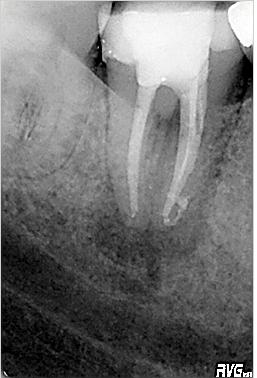

Röntgenologischer Ausgangsbefund im August 1996 bei Zahn 44 mit chronisch apikaler Parodontitis; Zustand vor umfangreicher ZE-Neuversorgung. Erste Therapie der Wahl ist in diesem Fall immer die konventionelle Wurzelkanalbehandlung ohne primär chirurgische Intervention

Wurzelfüllung im Januar 1997 in lateraler Kondensation mit normierter Guttapercha und AH 26. In der gleichen Sitzung wurde ein Titanstift adhäsiv inseriert mit dessen Hilfe der adhäsive Aufbau des Zahnes erfolgte

Langzeitkontrolle (definitiver Zahnersatz im April 1997) knapp vier Jahre nach Wurzelfüllung im Juni 2000 mit röntgenologischer vollständiger Ausheilung